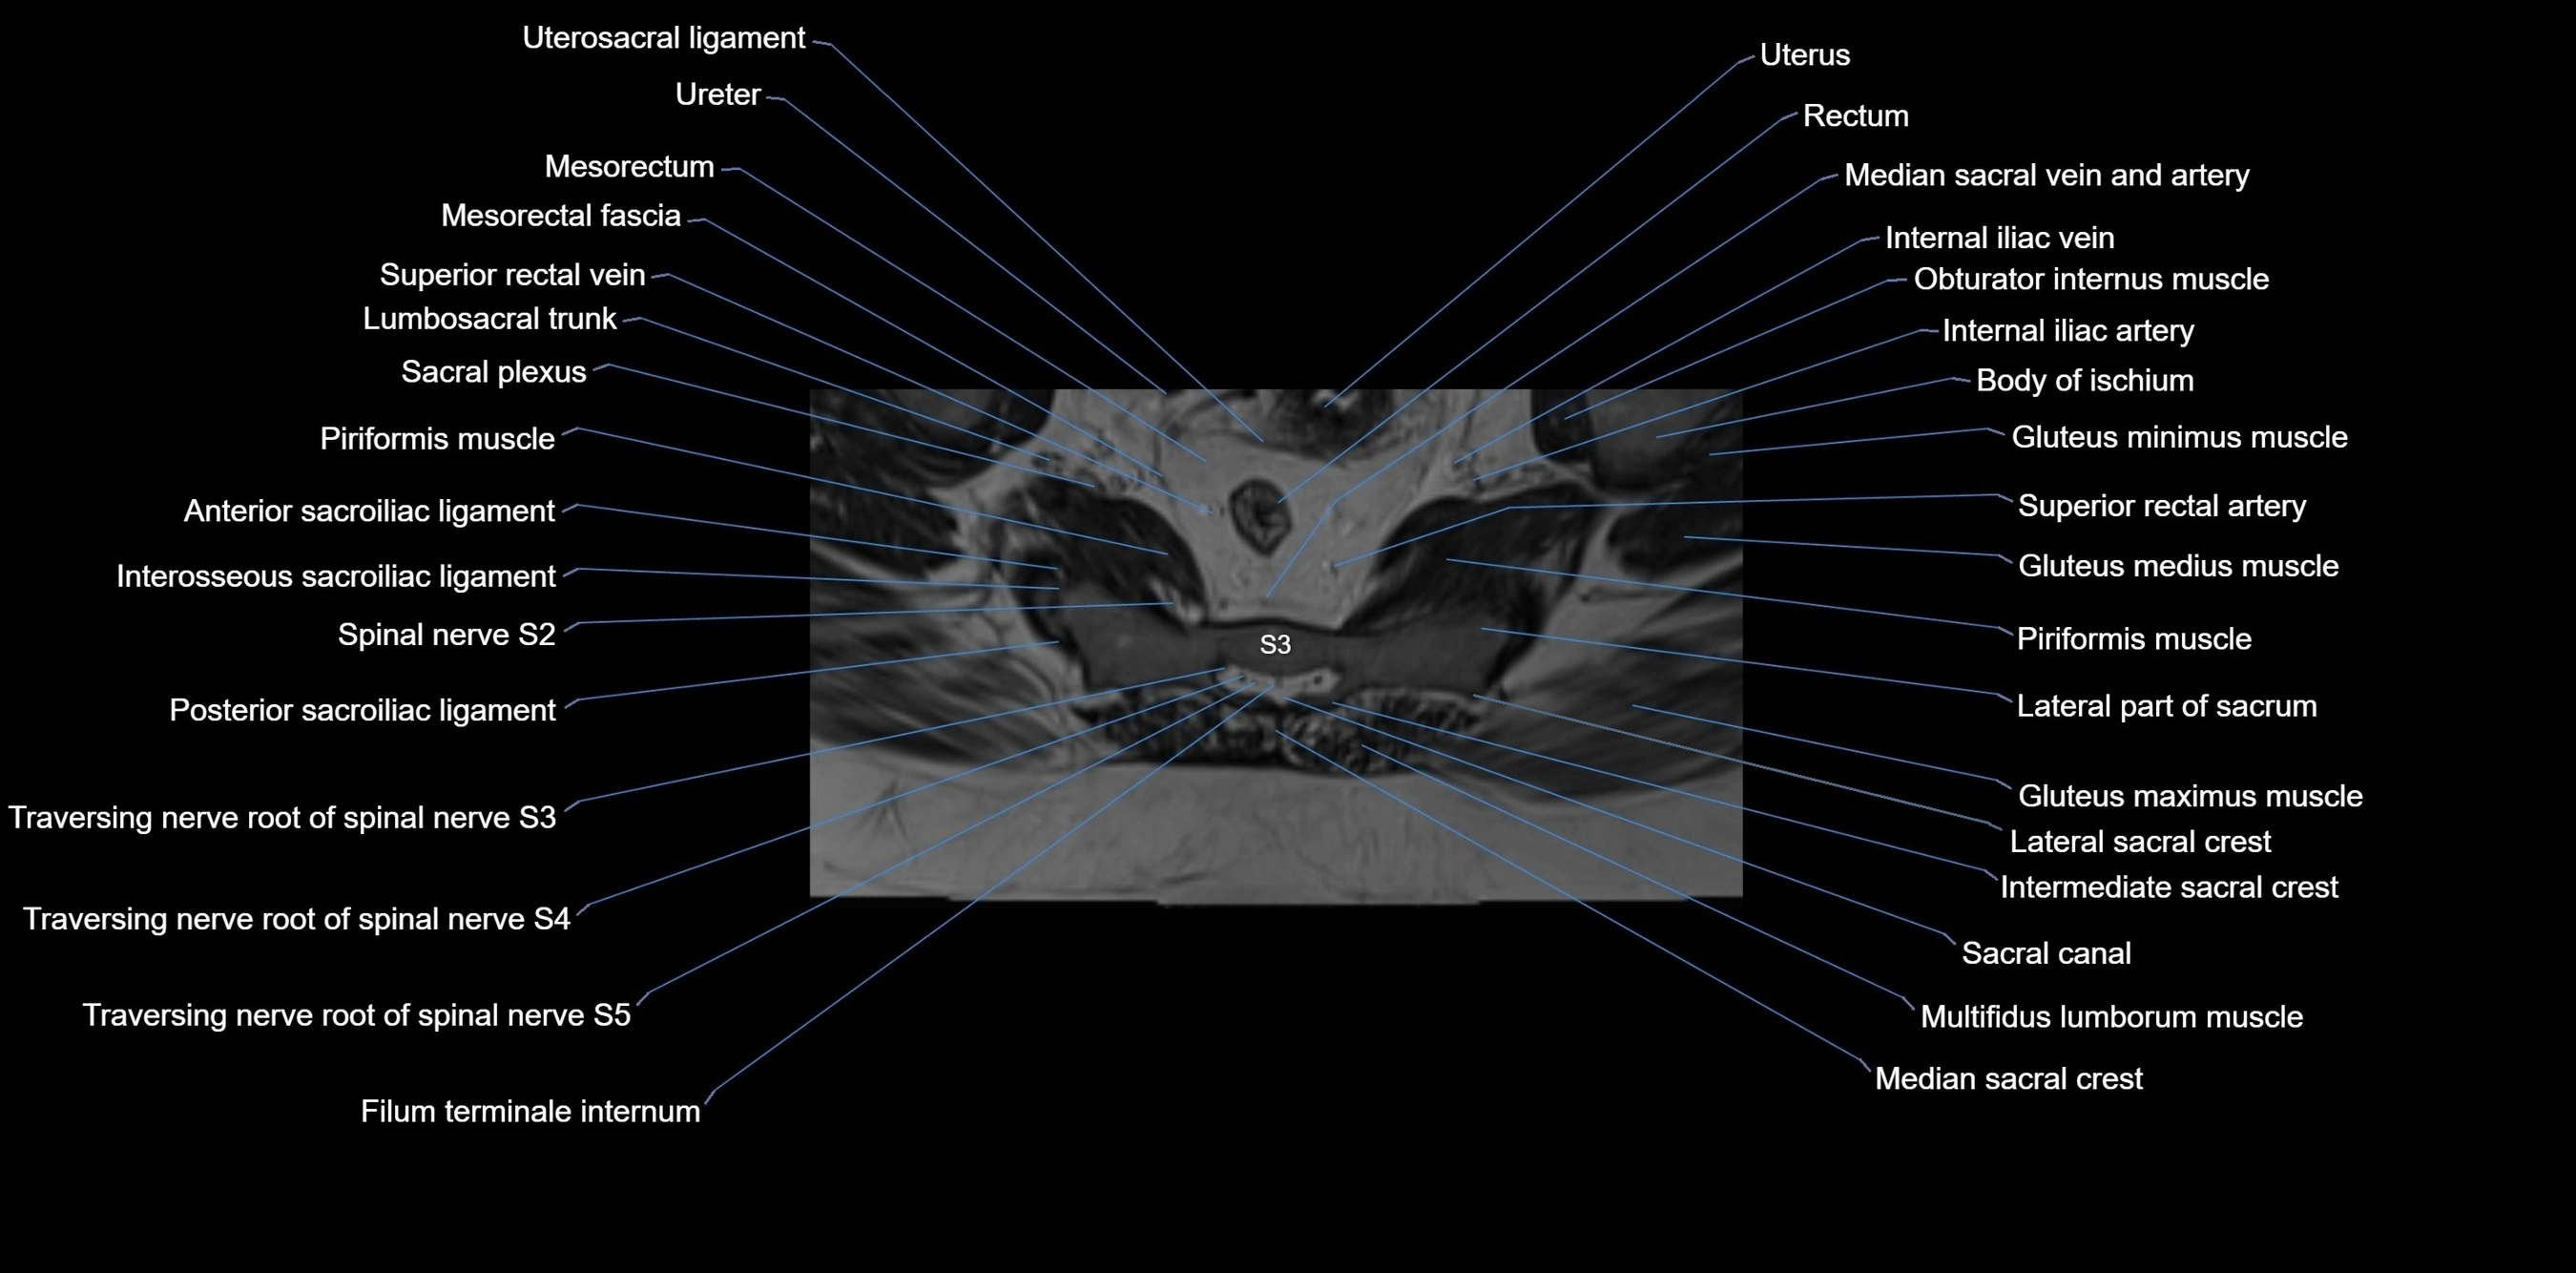

MRI Appearance

T1-weighted images:

• Cortical bone appears very low signal (dark); marrow shows intermediate signal

• Iliac fossa fat is bright against low-signal cortex

T2-weighted images:

• Cortical bone remains dark

• Marrow signal varies depending on fat content; edema or tumor shows hyperintensity

STIR:

• Suppresses fat, making bone marrow edema, fractures, or infiltrative lesions appear bright

• Excellent for trauma, sacroiliitis, and metastatic evaluation

T1 Fat-Saturated (Pre-contrast):

• Marrow: intermediate signal, fat suppressed

• Useful for detecting subtle marrow abnormalities adjacent to iliac cortex

T1 Fat-Saturated Post-Contrast (Gadolinium):

• Enhances vascularized structures, marrow pathology, tumors, and inflammatory changes

• Highlights soft tissue or bone invasion in pelvic neoplasms

MRI Non-Contrast 3D Imaging:

• Provides 3D morphology of iliac wing, crest, and articulations

• Used in preoperative planning for pelvic surgery and trauma reconstruction

MRI image

image